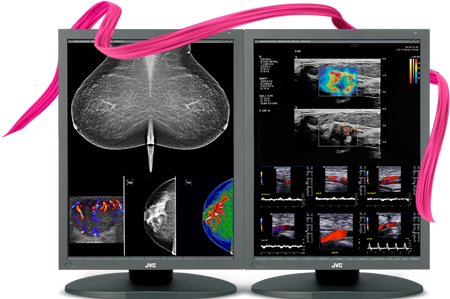

Barco Nio Fusion MDNC-12130 12MP 31" Color Tomosynthesis 3D-DBT Mammography Display

Barco Nio MDNC-6121 5MP 21" Color LED Mammo 3D-DBT Breast Imaging Display

Barco Nio MDNG-5221 5MP 21" Grayscale LED 3D-DBT Mammography Breast Imaging PACS Display

Barco Coronis MDMG-5221 5MP 21" Grayscale Tomosynthesis 3D-DBT Mammography Display

Barco Coronis UNITI MDMC-12133 12MP 33" Tomo Color LED Mammo 3D DBT PACS Display

Eizo RadiForce RX850 8MP 31" Fusion Color LED Mammo 3D-DBT Breast Imaging Display (RX850-BK)